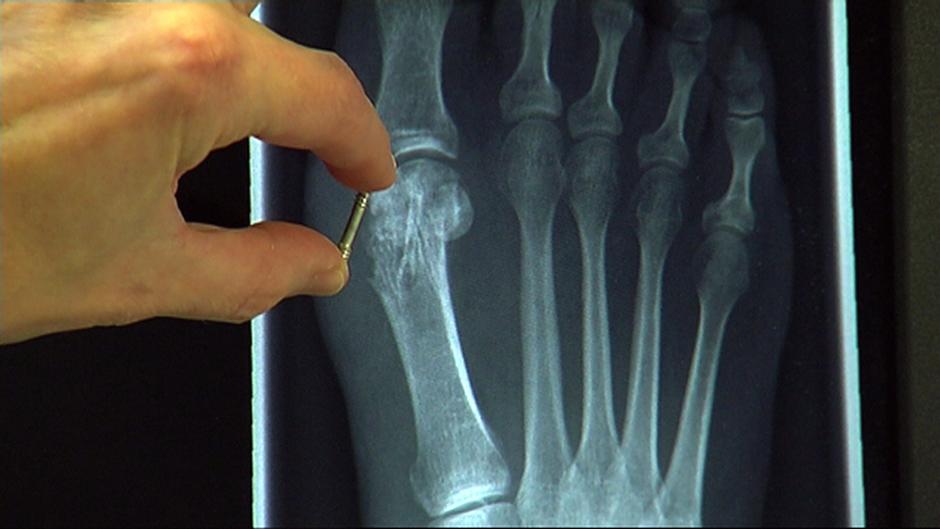

لكن الآن، وبفضل البرغي العظمي، أصبح من الممكن تقليص هذه المعاناة. على الظاهر، يصعب تمييز البرغي العظمي عن البرغي العادي، فهو مدور وطوله ثلاثة سنتيمترات، إلا أن سره يكمن في كونه مصنوع من سبيكة من المغنيسيوم تتحول إلى نسيج عظمي يذوب في الجسم خلال عام ونصف، حسبما تشرح شتوِكتنبورغ كولزمان، أخصائية الجراحة العظمية في ألمانيا، مضيفة بالقول: "يساعد هذا النوع الحديث من البراغي على استقرار العظام جيداً، ما يتيح التئامها جيداً".

ولا يقتصر استعمال البرغي في علاج الكسور فحسب، إذ من الممكن استخدامها أيضاً في تقويم العظام، فكثيراً ما يستخدم في علاج إنحراف إبهام القدم.

واحتاج الباحثون الألمان إلى 12 عاماً تقريباً لتطوير هذا البرغي، وأهم ما يميزه هو أنه يعزز تكوين أنسجة العظام الذاتية، فضلاً عن أنه لا يسبب الحساسية، لأنه مصنوع من مواد مستقاة من الجسم ولا داعي لإزالتها لأنها تذوب تلقائياً، على حدّ قول الطبيبة كولزمان.